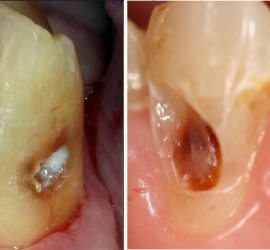

Аномалии строения и пороки развития зубов Пороки тканей зуба многообразны, они могут проявляться изолированно и сочетаться с аномалиями строения и пороками развития органов и систем всего детского организма, в том числе челюстно-лицевой области. Ткани зуба имеют эктодермальное (эмаль) и мезодермальное (дентин, пульпа, цемент) происхождение. В связи с этим пороки эмали […]